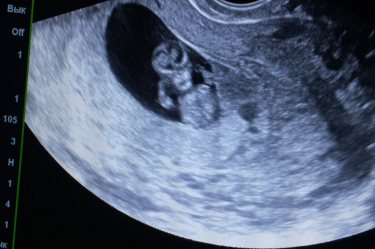

Остался один из двух, но очень сильный 💪 😁 10недель 3дня, очень ждём и любим❤️🤪 всех с наступающим Новым годом, и всем счастья🌸😁

Я не понимаю ...а почему у него такие ручки мощные ...для такого срока )))обычно их ели видно и они не до конца сформированные ...главное что по узи все хорошо ??